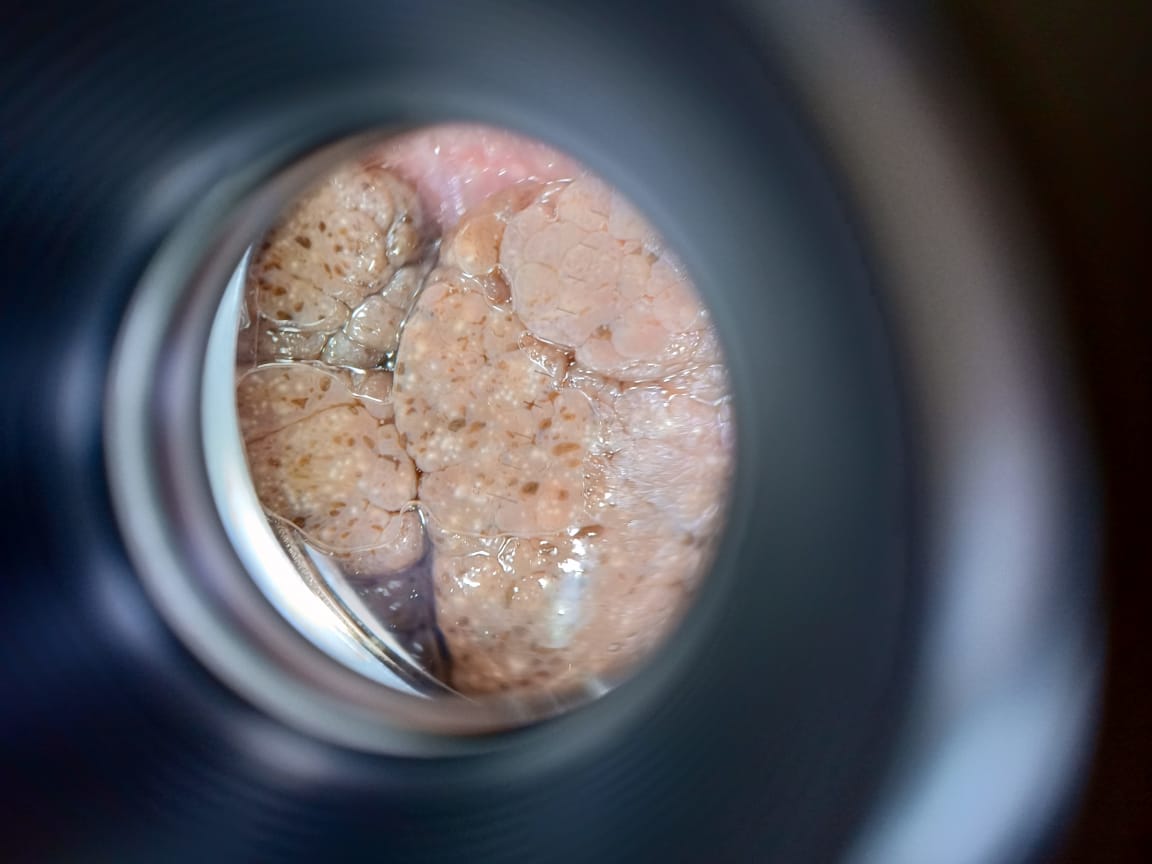

Жители Актау прошли бесплатное обследование родинок, пигментных пятен с помощью дерматоскопа в рамках всемирного Дня меланомы.

Меланома представляет собой злокачественные новообразования на коже, которые развиваются из пигментсодержащих клеток меланоцитов. Появление небольших родинок и пигментированных пятен зачастую может представлять раковое образование – меланому.